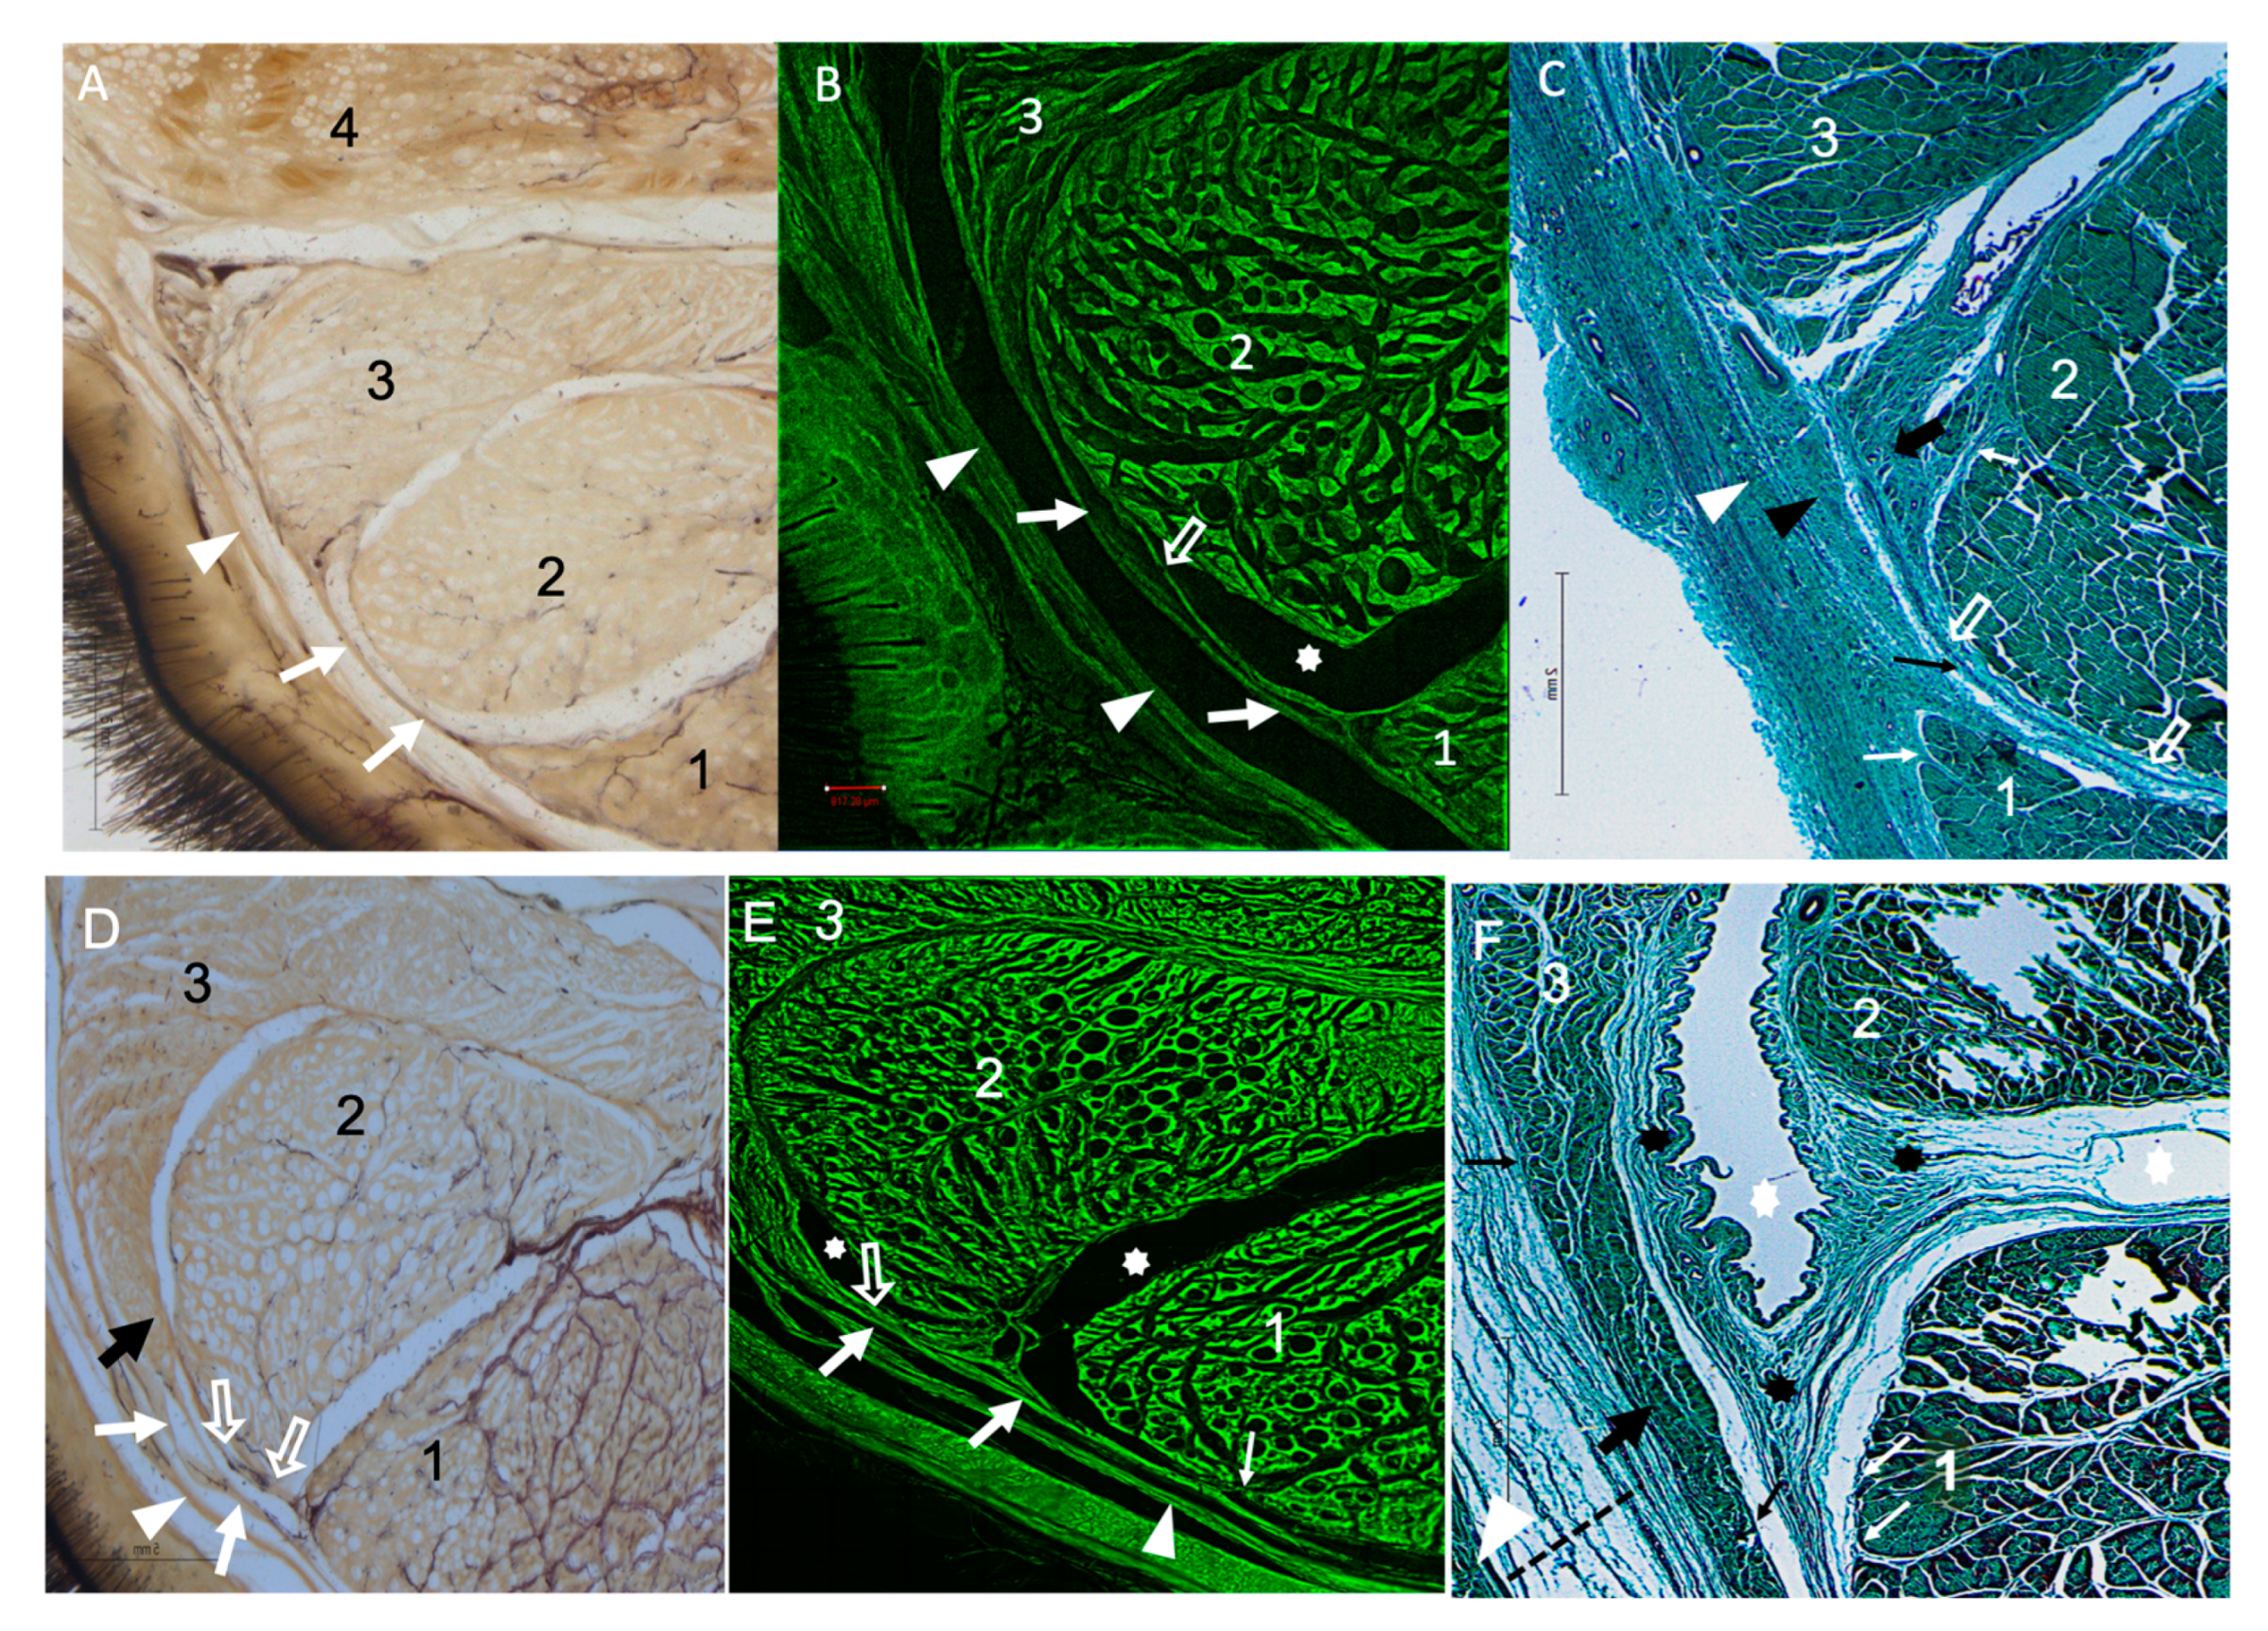

3.2. Cross-Sectional Anatomy

3.3. Morphometric Analysis